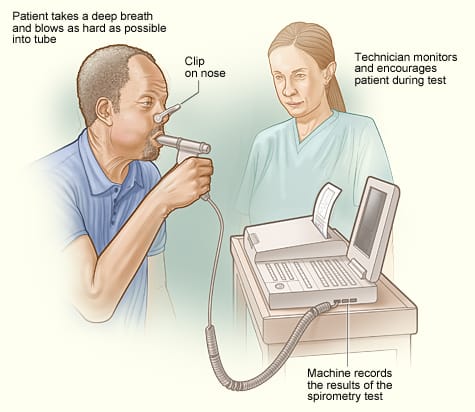

Spirometry (સ્પાઈરોમેટ્રી):

- સ્પાઈરોમેટ્રી એ એક પ્રકારનું લંગ ફંક્શન ટેસ્ટ છે જે આપણે કેટલી અમાઉન્ટમાં એર ઇન્હેલ અને એક્સેલ કરીએ છીએ તે મેઝર કરે છે આ ઉપરાંત કેટલા રેટથી (ફ્લો થી) ઇન્હેલ અને એક્સેલ કરીએ છીએ તે મેઝર કરે છે.

- સ્પાઈરોમેટ્રી ટેસ્ટમાં સ્પાઈરોમીટર ઇન્સ્ટ્રુમેન્ટનો ઉપયોગ કરવામાં આવે છે જેમાં ટ્યુબ દ્વારા માઉથ પીસ કનેક્ટેડ હોય છે અને આ માઉથ પીસ દ્વારા પેશન્ટની એર ઇન્હેલ અને એક્સેલ કરવાનું કહેવામાં આવે છે અને સ્પાઇરોમીટરમાં થતા ચેન્જીસને ઓબ્ઝર્વ કરવામાં આવે છે.

- આ ટેસ્ટ કરતી વખતે નોઝને ક્લિપ કરી દેવામાં આવે છે.

- સ્પાઈરોમેટ્રીની મદદથી રેસ્પાયરેટરી કંડીશન જેમ કે અસ્થમા અને COPD ને અસેસ કરી શકાય છે.